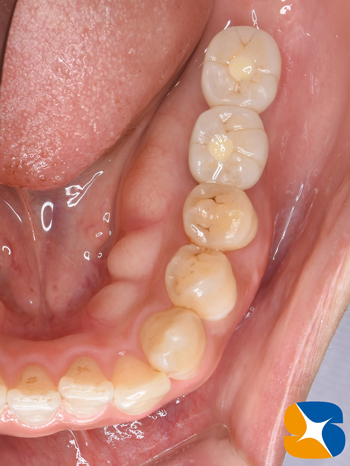

施術より3ヶ月後、インプラント完成。

施術から3ヶ月後、インプラント完成。

適合の良くなかった前歯もセレックを使って、オールセラミックスに順次やり変え。